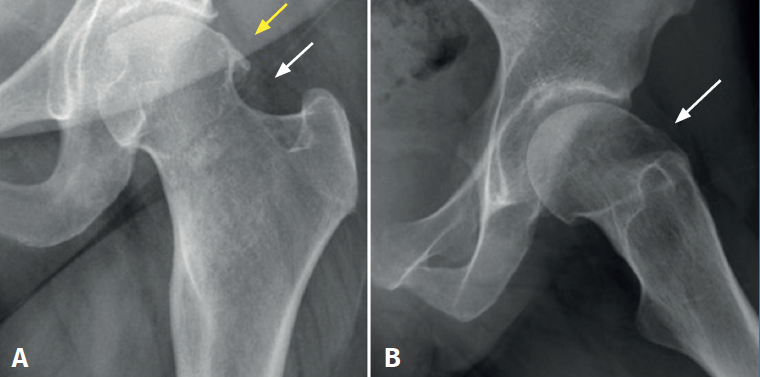

We present the case of a 49-year-old woman with left hip pain and limping for approximately two years. Her history indicated surgery of the hip in adolescence, though the cause of surgery was not known, and no documentation was available. The physical examination revealed pain in response to flexion and internal rotation of the hip, with positive anterior impingement manoeuvring. The plain X-rays (Figure 1) showed large, isolated exostosis in the femoral head-neck transition zone, with no evidence of associated exophytic lesions. The magnetic resonance imaging study revealed exostosis of the anterolateral surface of the femoral neck, measuring 21 × 14 mm in diameter (Figure 2), with signs suggestive of rupture of the anterosuperior labrum.